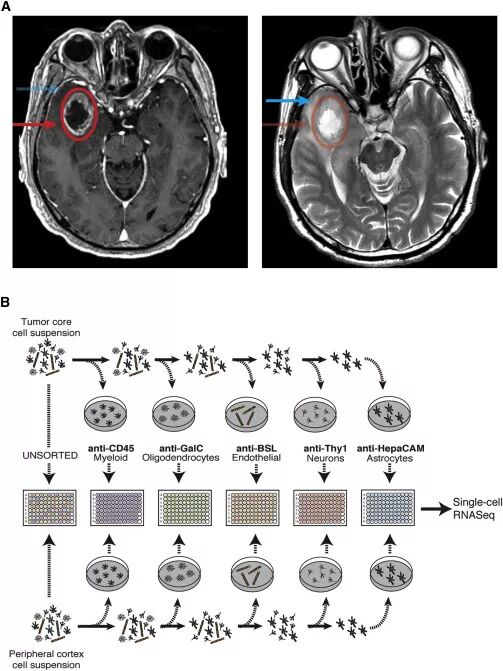

研究者从每例GBM患者的肿瘤核心和肿瘤外围两个不同的位置采集样本(图1A)。利用各种类型细胞的特异性标志物纯化各个细胞亚群,包括神经元、星形胶质细胞、髓系来源细胞和血管内皮细胞等,有助于捕获迁移到瘤周组织中的肿瘤细胞和比较肿瘤微环境中各种神经细胞和免疫细胞的转录组水平变化。分选后的细胞置入96孔板培养,并进行RNA测序(图1B)。

图1. A.右颞极GBM患者的MRI-T1增强(左侧)和T2(右侧)成像显示,肿瘤核心部位强化(红色圆圈,箭头),瘤周部位T2高信号(蓝色箭头);B.实验示意图。